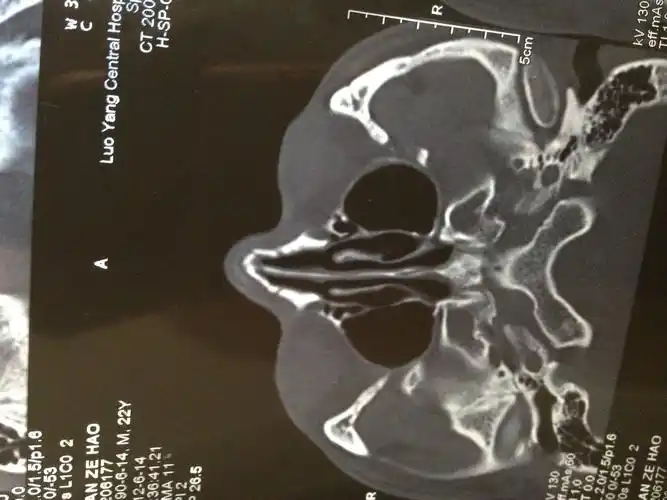

鼻部向左侧倾斜,双侧鼻骨可见骨折线影,部分成角畸形,双侧上颌骨额突